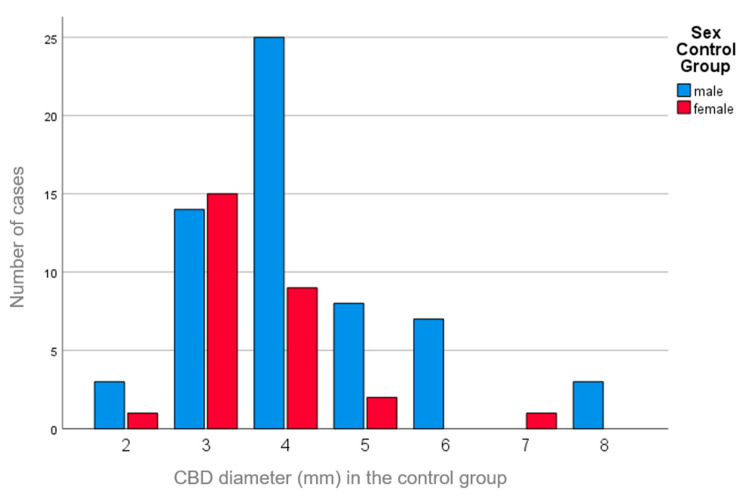

There was a weak correlation between the CBD diameter and sex (study group, r = 0.066, p = 0.462; control group, r = 0.244, p = 0.022), with slightly larger CBD diameters observed in males (Figure 3).

In our study, we observed diameters of 2–8 mm in the control group (median diameter of 3 mm in females and 4 mm in males). Although the control group consisted of only 88 individuals, it seems that the CBD diameter is smaller in corpses.